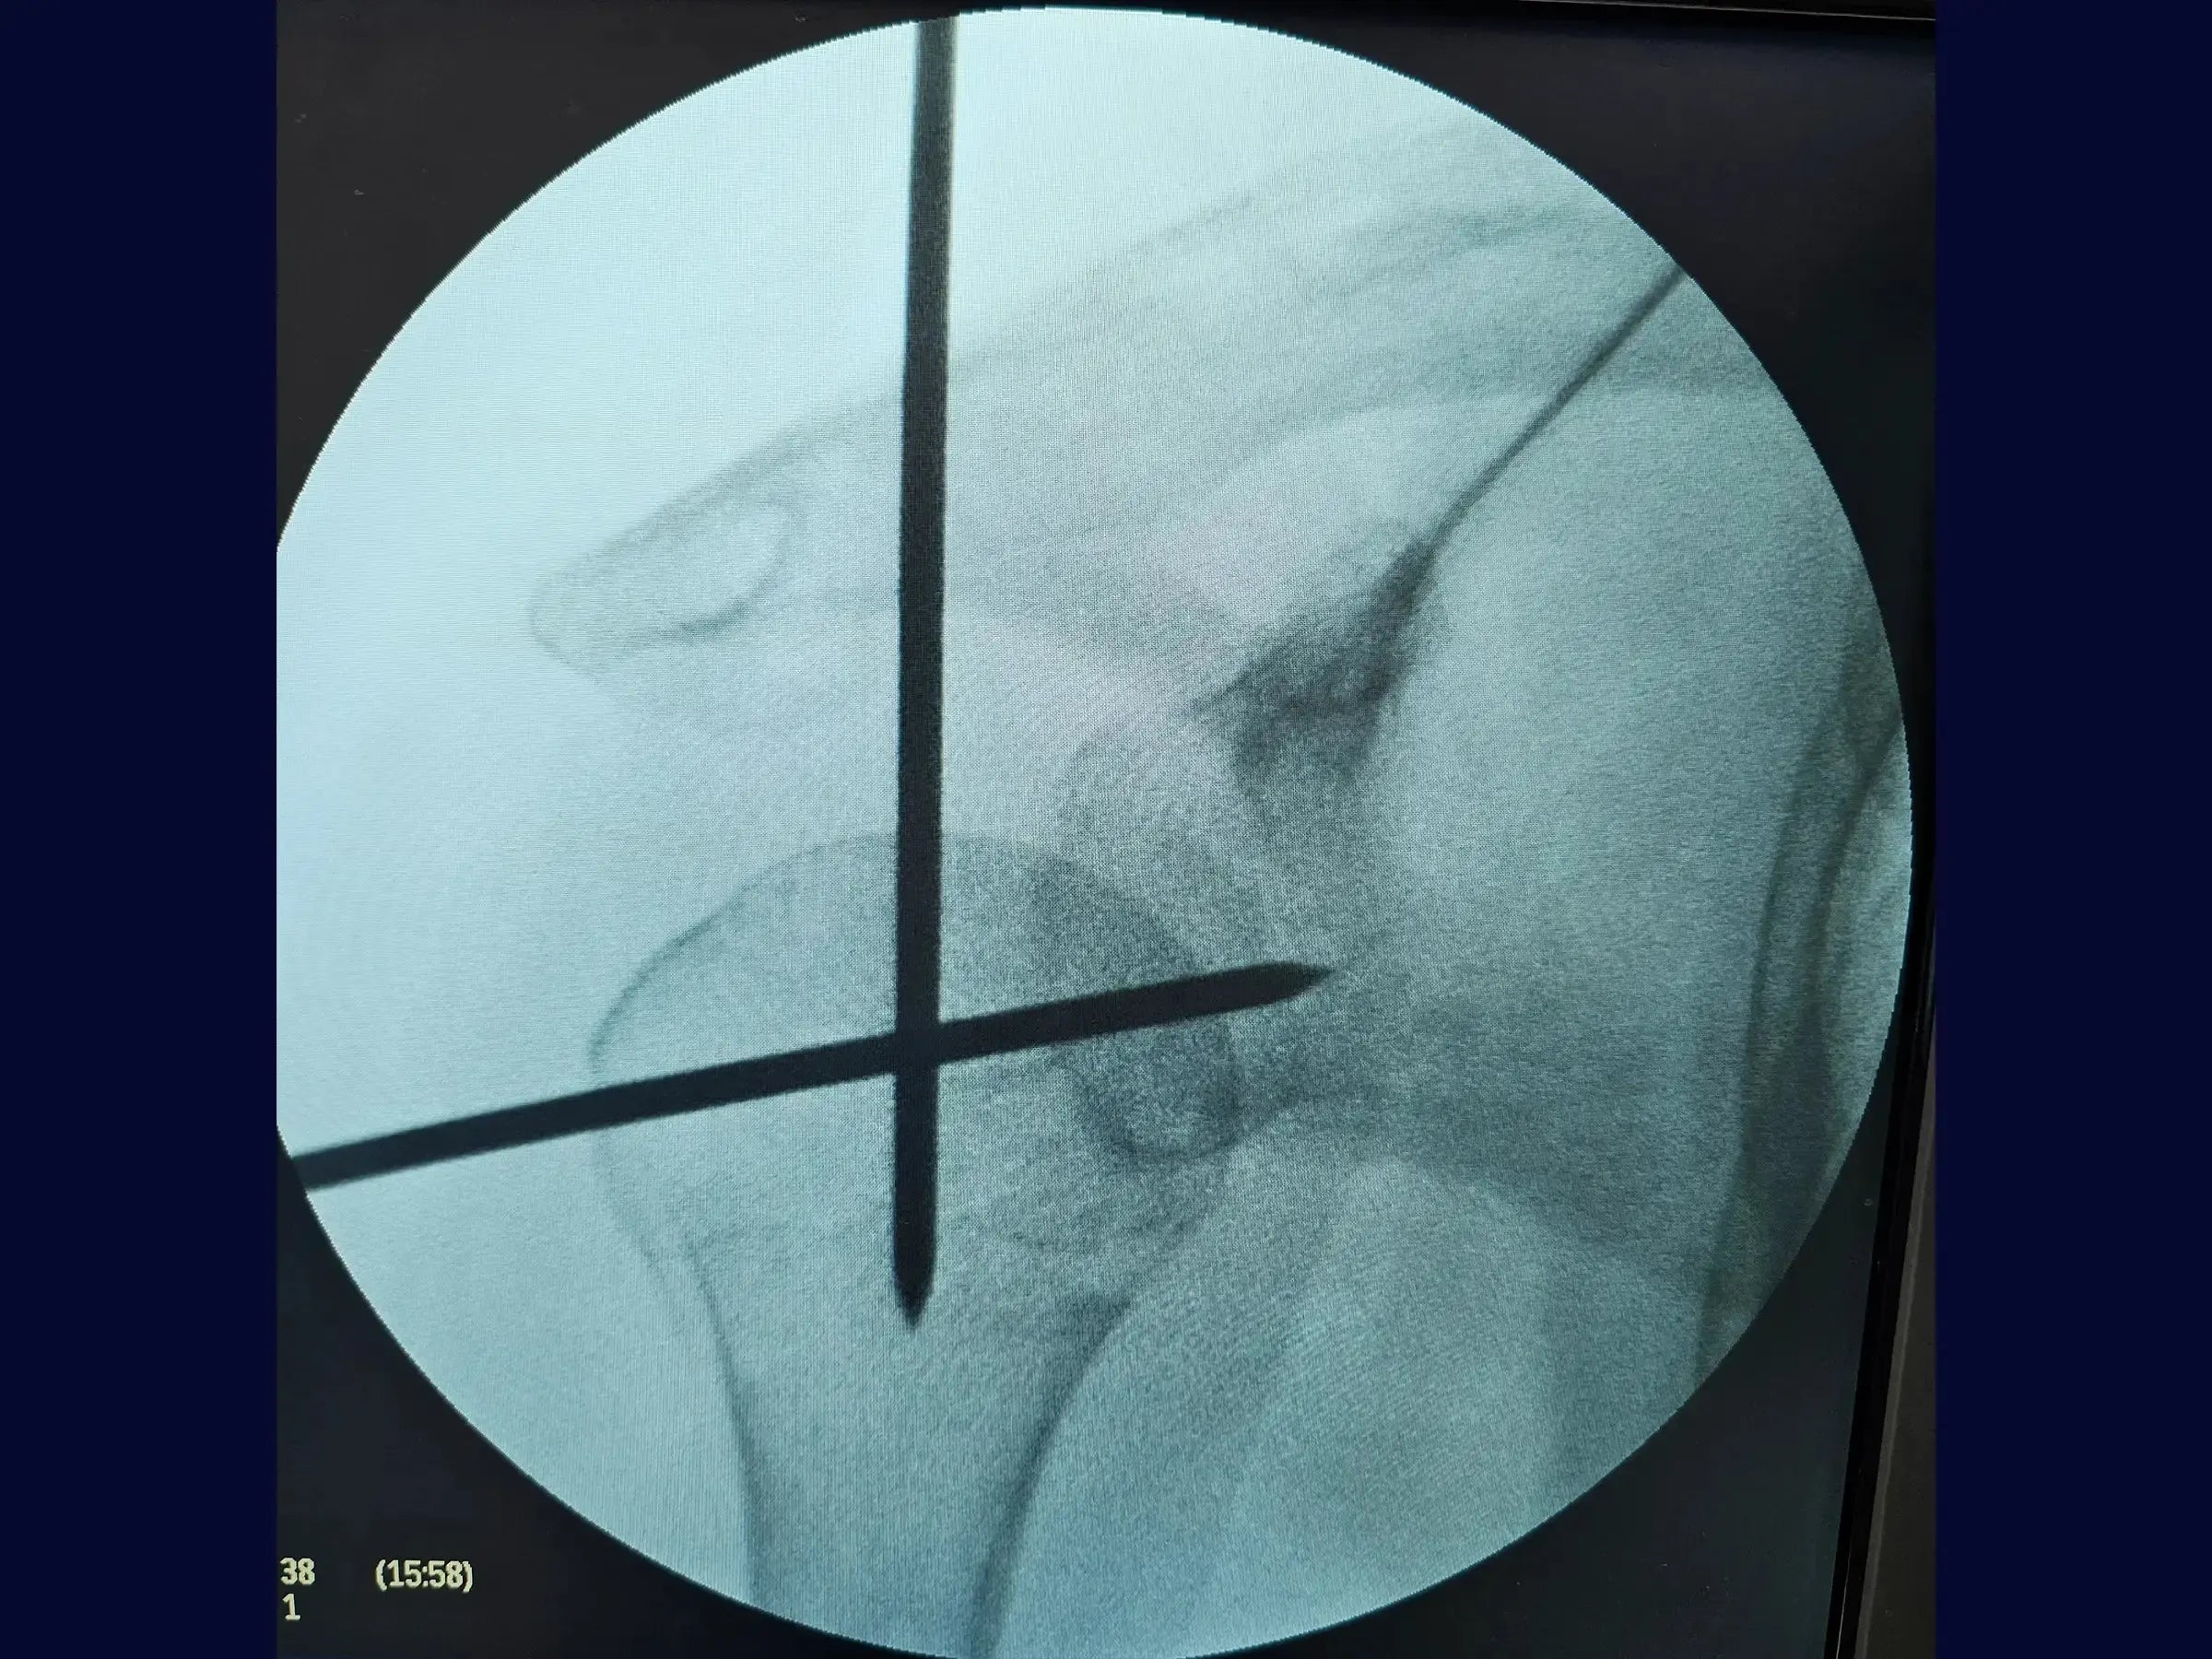

- Mensuração precisa da haste intramedular.

- Mensuração Precisa da Haste Intramedular: Protocolos de mensuração utilizando um guia externo, com atenção às particularidades anatômicas do úmero distal para evitar subdimensionamento ou sobredimensionamento do implante.

- Técnica de Inserção da Haste Intramedular: Abordagem para introdução manual da haste, visando prevenir o uso de martelo e reduzir o risco de fraturas iatrogênicas.